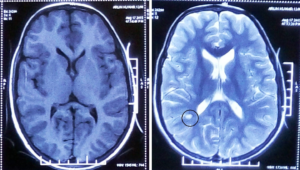

ПСПЕ – прогресуюче нейродегенеративне захворювання центральної нервової системи, що прогресує, – спричиняє коревий вірус. Воно розвивається в середньому в одного-двох пацієнтів із 10 тисяч тих, хто перехворів на кір. ПСПЕ відносять до повільних вірусних інфекцій. Після первинного зараження настає безсимптомний період, який зазвичай триває 5-10 років, але в деяких випадках може варіюватися від одного місяця до 27 років. Мутований вірус кору поширюється мозком, спричиняючи спочатку малопомітні порушення в інтелекті та психіці, а потім погіршення сенсорних і рухових функцій, що зрештою закінчується смертю.

Автори роботи виявили два основних типи геному корового вірусу, які були присутні у всіх досліджених зразках. За словами доктора Каттанео, комбінація характеристик мутантних геномів колективно сприяла поширенню вірусу з первинного місця інфікування – лобової кори – по всьому головному мозку.